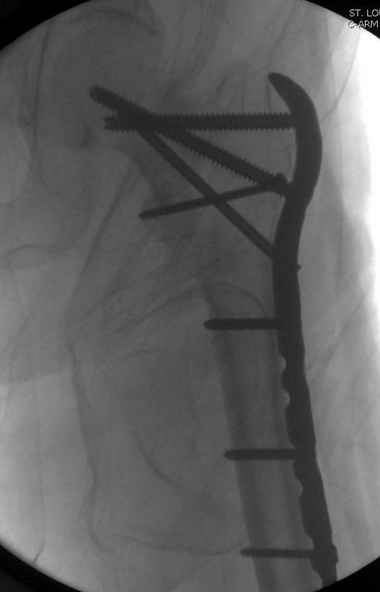

Применили проксимальную Synthes Locking plate, из-за множественных фрагментов посчитали более приемлемым в этом случае (клиника университетская, резиденты должны имет возможность созерцать разные варианты остеосинтеза).

Также старался минимизировать доступ на уровне перелома с субвастус доступом, диафиз фиксирован перкутанно, не стали гонятся за малым вертелом, как смог зафиксировал.

Перелом из четырех фрагментов, не стабильный (лекция Michael R. Baumgaertner, http://www.hwbf.org/ota/bfc/baumg/exp.htm), нужна стабильная фиксация.

Фиксация таких нестабильных чрезвертельных и reverse obliquity субтрохантерик переломов всегда была сложной задачей и ранее использовали Blade Plate. Но многие локальные общие ортопеды, к которым, в основном поступают такие больные, имели трудности с применением импланта, где необходимо было точная калькуляция по введению Blade и поэтому Synthes разработал Proximal Locking plate как альтернативу, где три проксимальные шурупа в разных направлениях создают концепцию угловой стабильности Blade Plate.

Со второго дня движения в суставе, контрольный осмотр через две недели и в зависимости от рентгенологического сращения, дозированную нагрузку с постепенным увеличением начнем через 5-6 недель.